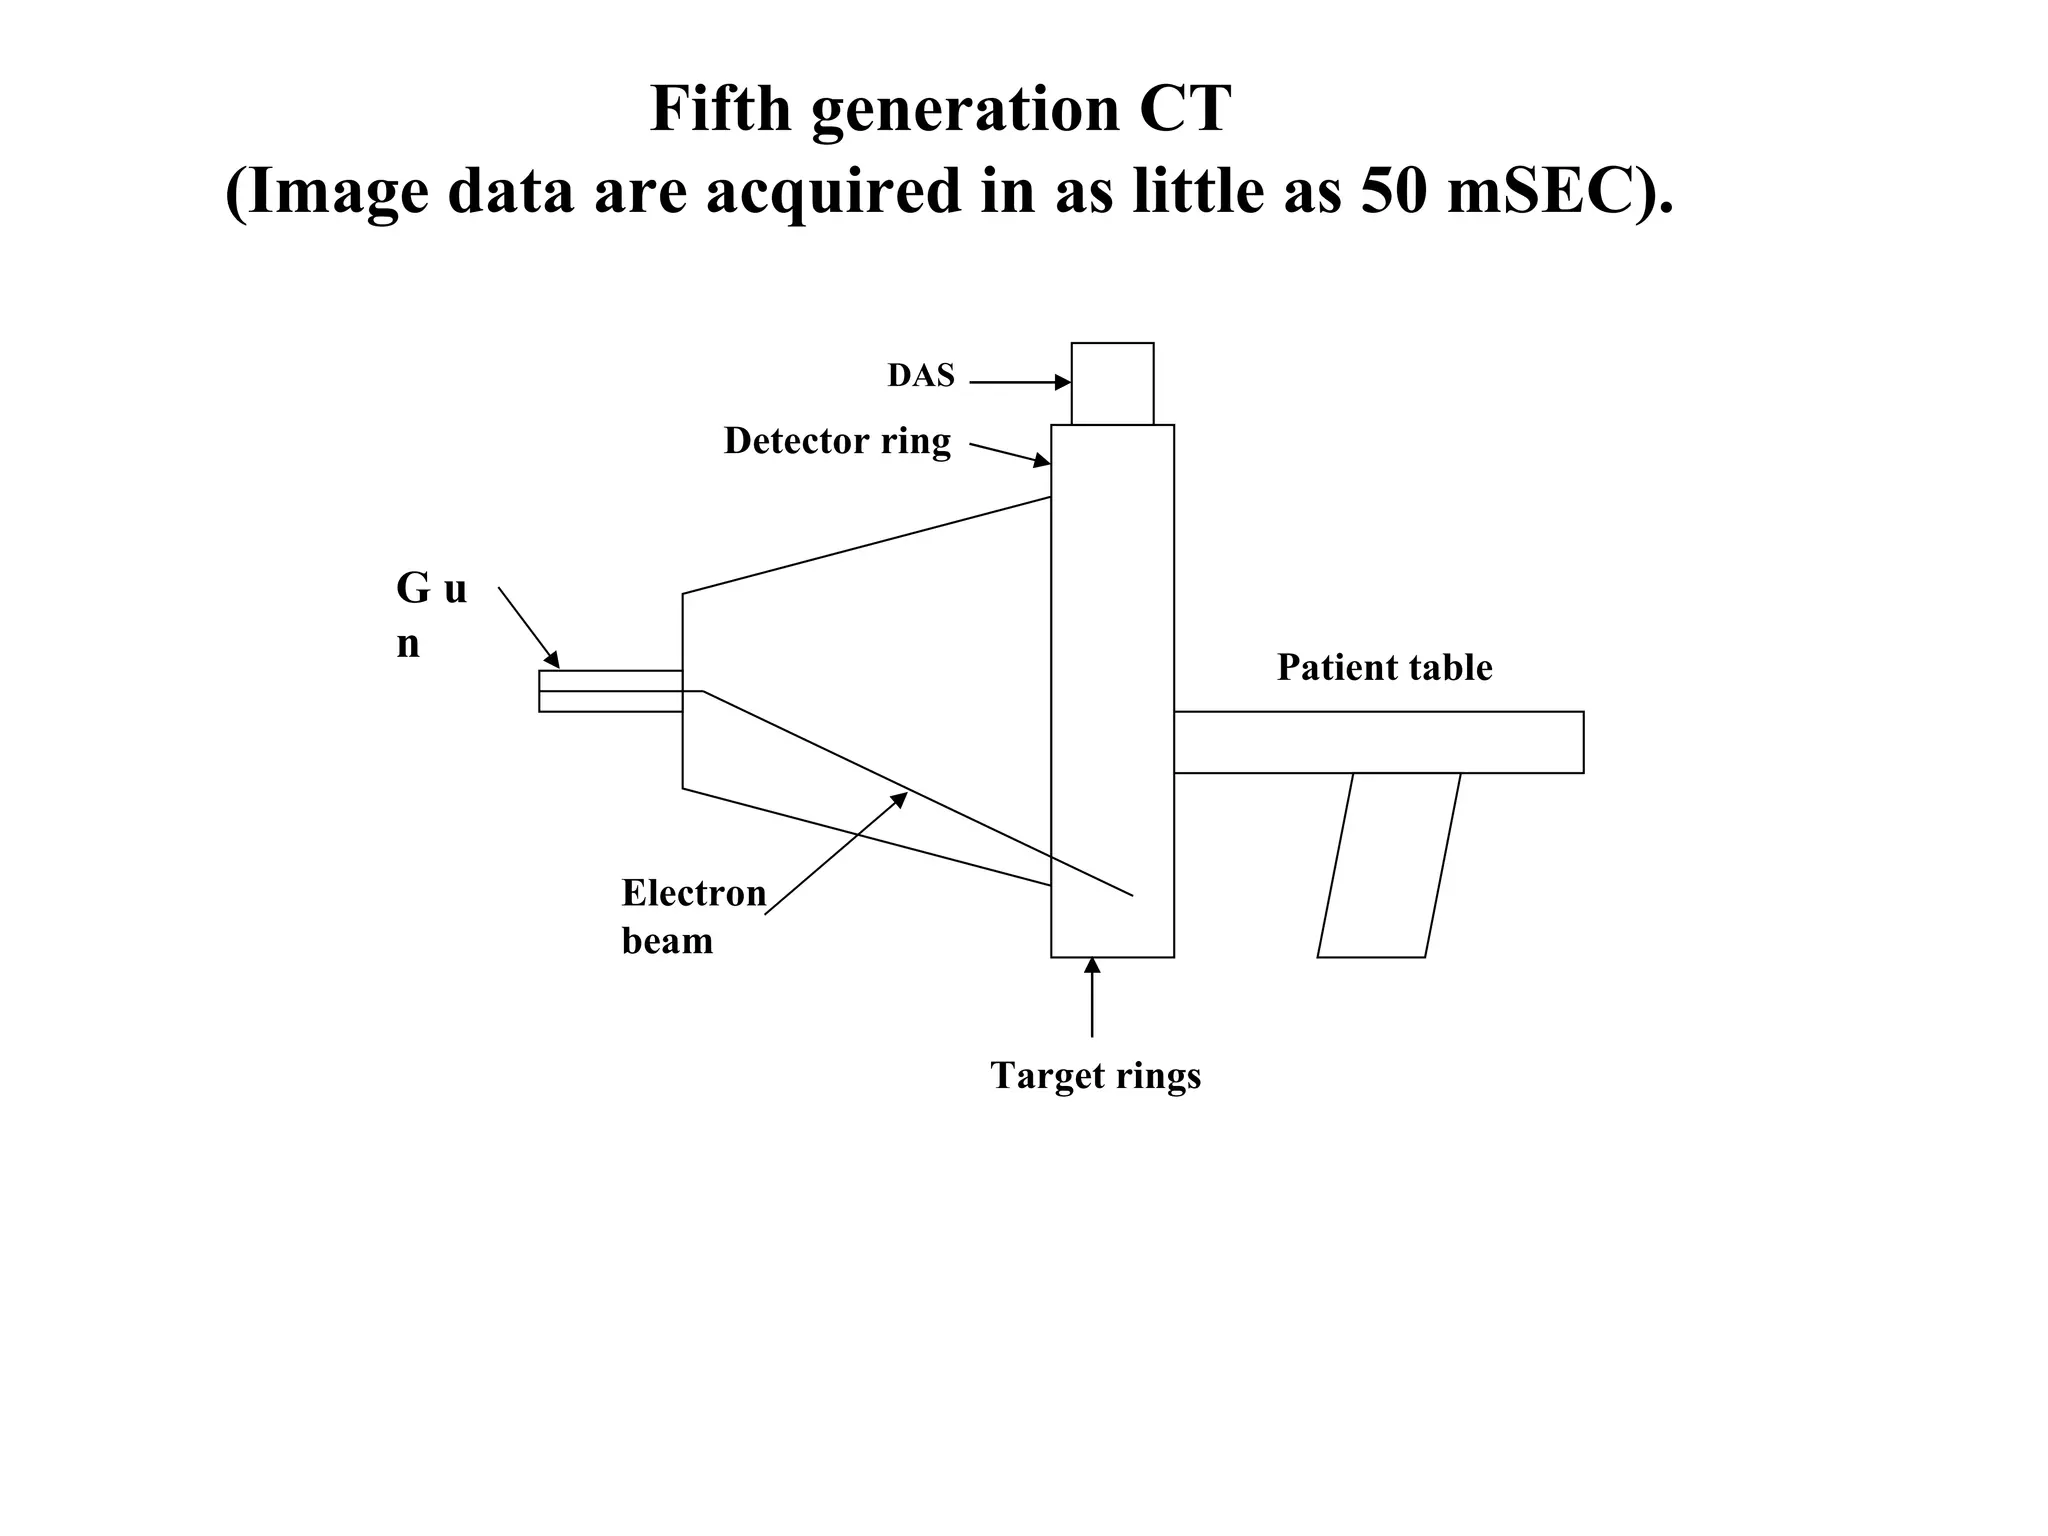

The document discusses various medical imaging modalities including x-rays, computed tomography (CT), and digital mammography. It describes the basic principles and historical development of these technologies, how images are formed, and what types of anatomical features and abnormalities they can detect. Key advances include the development of digital systems that allow image manipulation and remote consultation. While promising, digital mammography still faces challenges around resolution and cost.